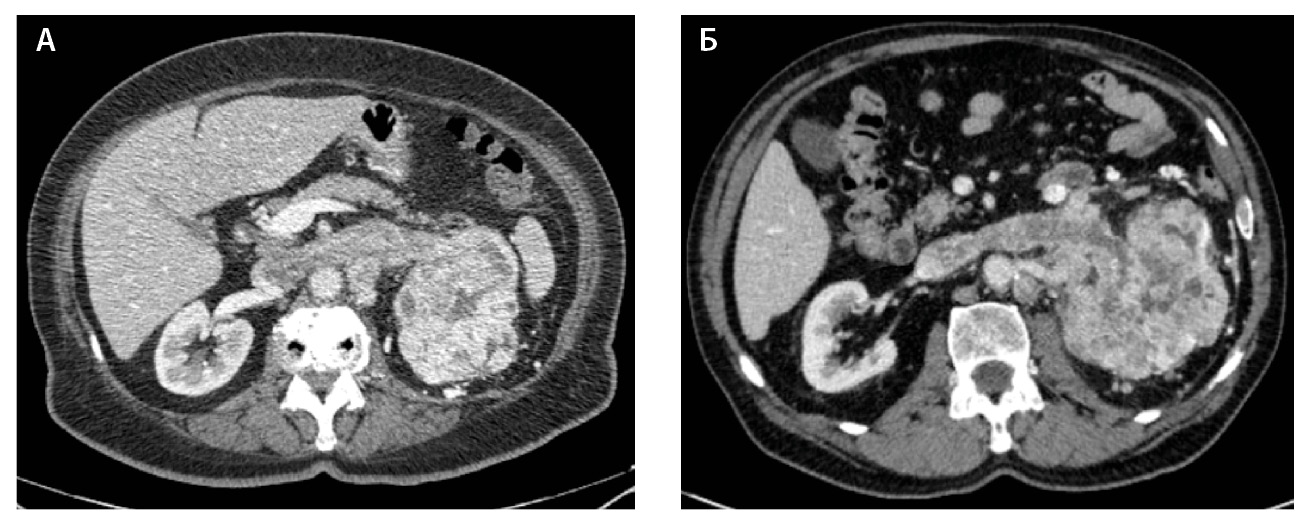

Компьютерная томография (КТ) с внутривенным контрастным усилением широко используется как метод диагностики и первичного стадирования скПКР. В настоящее время наиболее значимыми характеристиками опухоли для предоперационного стадирования и планирования хирургического лечения скПКР признаны расположение, размер опухоли и признаки ее инвазивного роста [3–6], а структура и характер контрастирования позволяют дифференцировать типы ПКР, но ни один из этих показателей не дает возможности достоверно прогнозировать степень дифференцировки опухоли. Структура скПКР любой степени дифференцировки, как правило, гетерогенная с наличием солидного и кистозного компонентов. Признаки инвазивного роста опухоли, наличие метастазов позволяют предположить низкую степень дифференцировки опухоли, однако не являются достоверными признаками. Как видно на рис. 1, скПКР разной степени дифференцировки по данным КТ выглядят практически идентично: в обоих случаях визуализируется опухолевый тромб в почечной вене с распространением в просвет нижней полой вены. Такие характеристики, как размер опухоли, пофазное накопление контрастного вещества и градиент накопления контрастного вещества при КТ-исследовании, также не являются строго специфичными для разных степеней дифференцировки скПКР (рис. 2).

Рис. 1. Светлоклеточный почечно-клеточный рак: А – Grade 4 (данные компьютерной томографии пациентки Б.), Б – Grade 2 (данные компьютерной томографии пациента Г.). На обоих снимках кортико-медуллярная фаза исследования: гиперваскулярная опухоль солидно-кистозного строения, замещающая паренхиму левой почки, опухолевый тромб в просвете левой почечной вены с распространением в нижнюю полую вену; метастически измененный регионарный лимфатический узел